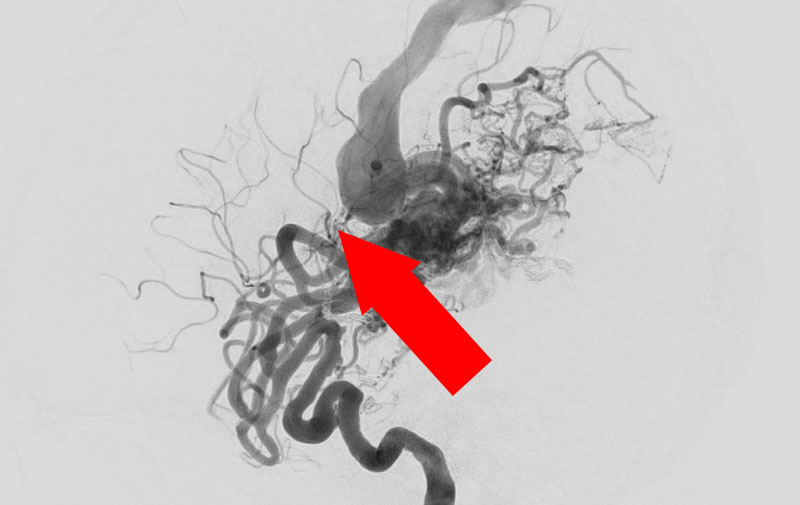

No.1585 手術前

No.1585 手術中

No.1585 手術後

'25年10月

脳動静脈奇形

50代

大阪府の病院